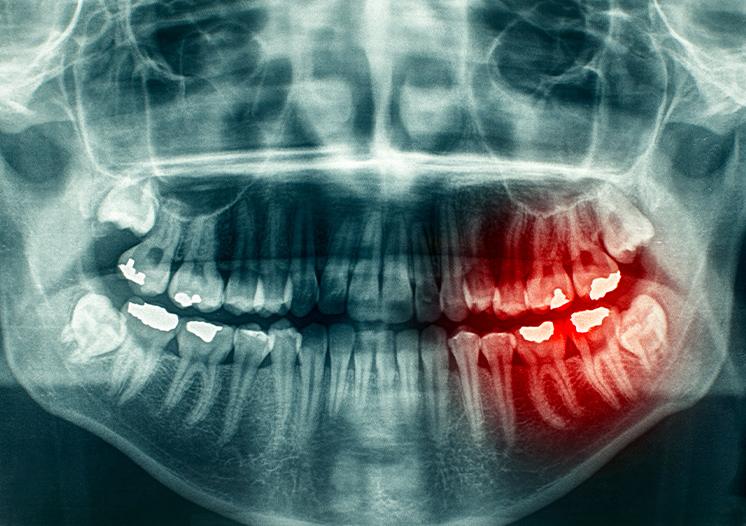

Before recommending wisdom teeth removal, we look at how your teeth are positioned and how they may affect your oral health over time. This may include reviewing digital X-rays, looking at how the teeth are developing, and talking through any symptoms you may be experiencing.

● Pain or pressure at the back of the mouth

● Swelling or irritation around the gums

● Impacted teeth that remain under the gums or bone